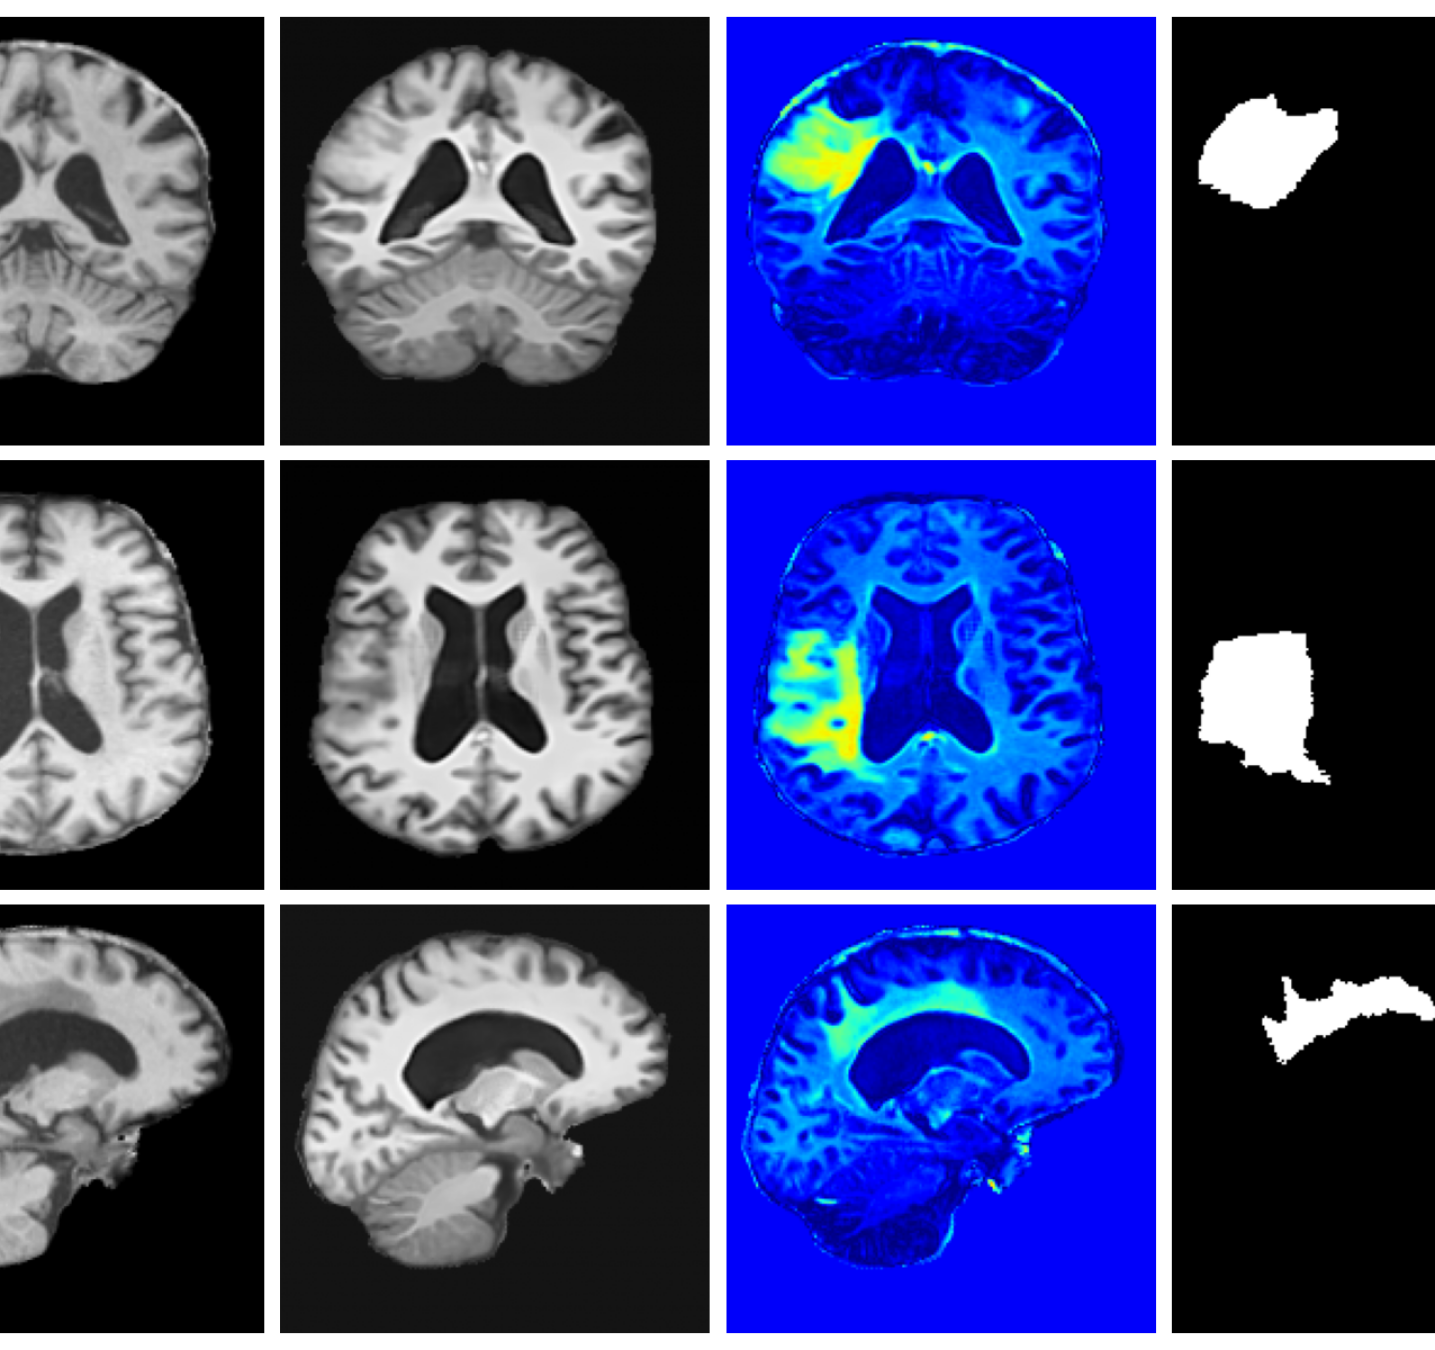

Qualitative T1w results are shown in Figure 2, with further examples for other modalities in Appendix A.8. LoHiResGAN and Res-SRDiff produce unrealistic images with severe artifacts, likely arising from bias fields, sharp intensity artifacts, and other noise not present during training. UniRes generates oversmoothed images, likely due to its TV prior and its reliance on information from multiple input modalities, whereas we apply it unimodally. Di-Fusion shows less pronounced but still notably blurry, voxelated reconstructions which lack the fine-grained details generate by our method. This is likely, in part, due to our use of synthetic rather than real noisy training data, which the method was designed for. As such data is scarce, and in our case unavailable, this requirement represents a significant limitation of Di-Fusion. SynthSR, whilst not as well as our method, does preserve key anatomical structures. However, our difference maps show reduced contrast, further supporting the strong quantitative results shown in Table 2.

A.8 Additional qualitative restoration results

Additional qualitative results for the Clinical dataset are given in Figures 7, 8 and 9, and for the Low-field dataset in Figures 10 and 11.